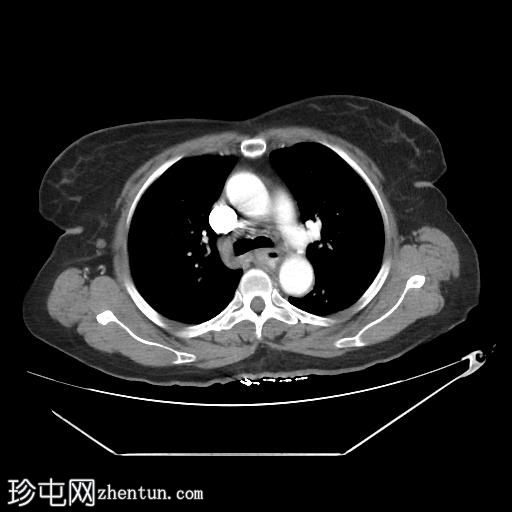

轴位增强扫描

动脉期

中段食管壁增厚,提示

肿瘤

浸润,长约10厘米。肿块与左主支气管后壁及降主动脉紧密接触。未见侵犯邻近结构的迹象,也未触及区域淋巴结肿大。